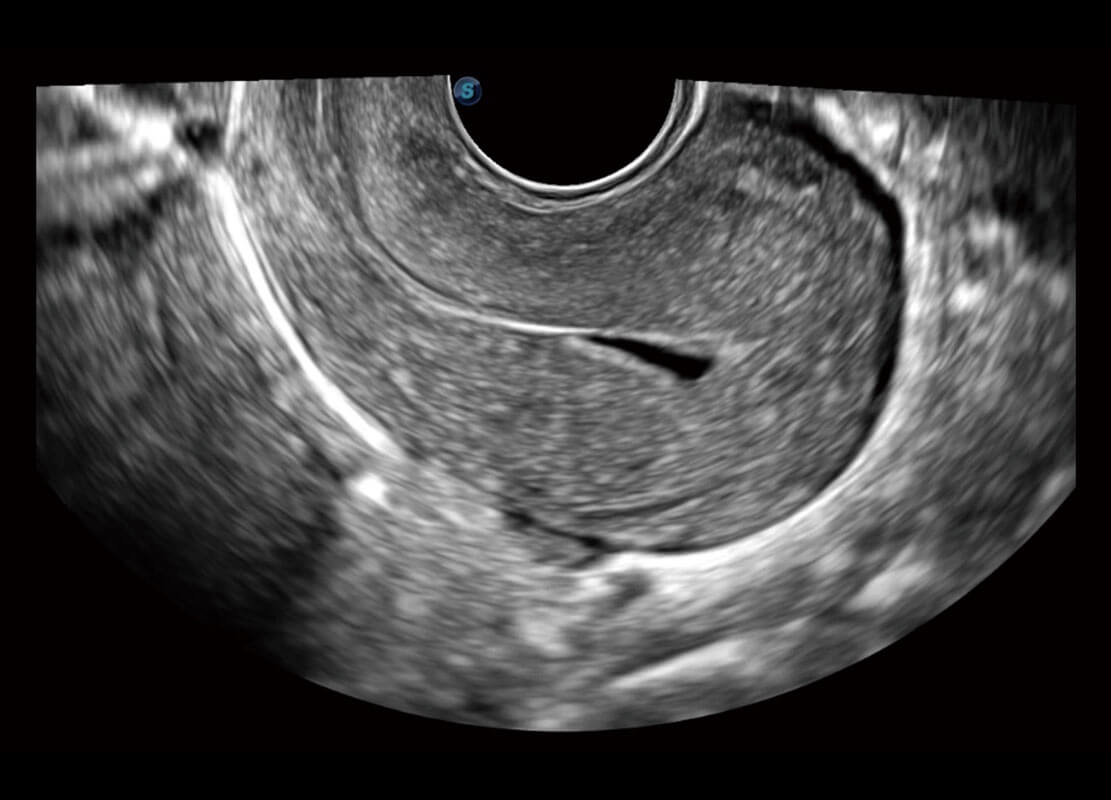

• 腔内妇科-宫腔分离

• 腔内妇科-卵巢